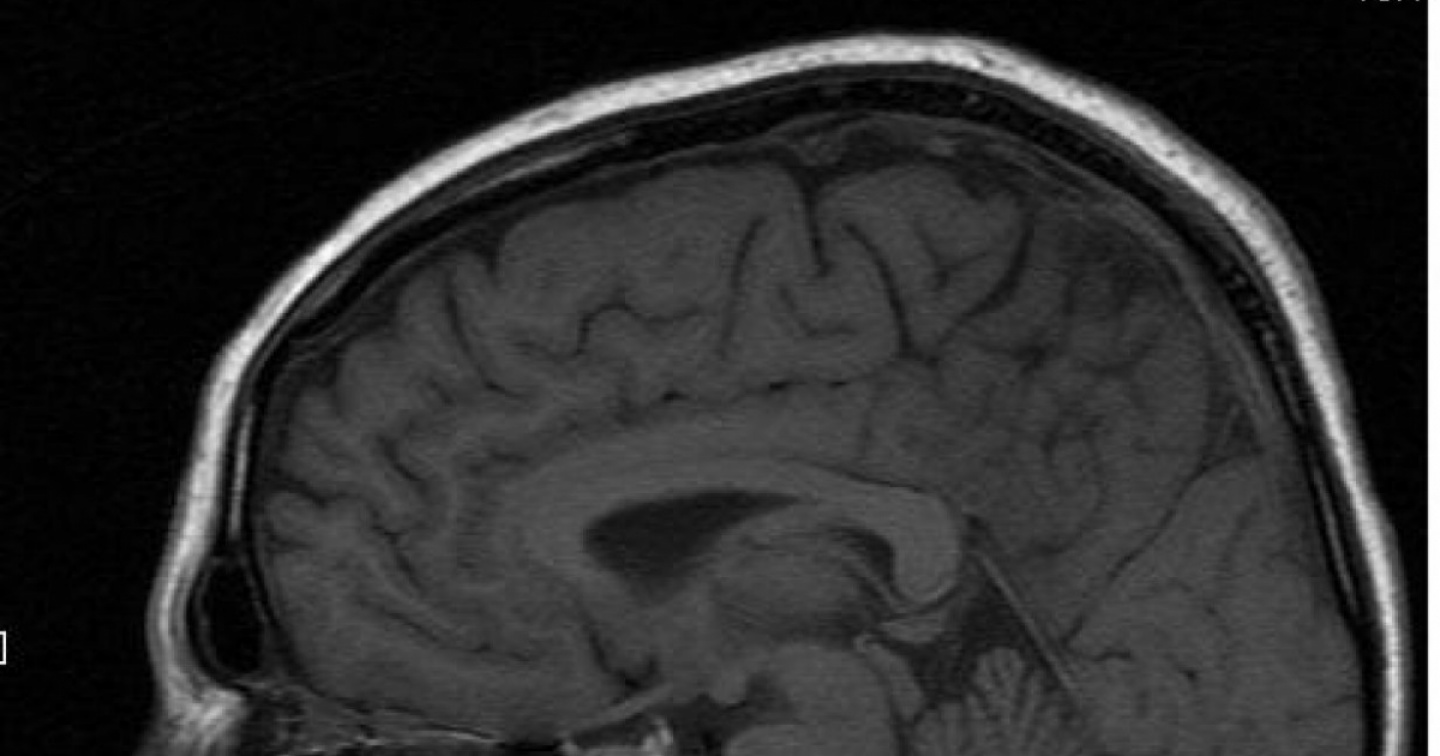

"Stiamo sviluppando qualcosa di simile all'elettrocardiogramma da sforzo, ma per esaminare il cervello invece del cuore", spiega Olaf Blanke, neuroscienziato dell'Epfl. Il ‘Robot ghost test’ è stato provato su 26 pazienti. È fra l'altro risultato che quelli con preesistenti allucinazioni di presenza sono più sensibili alla stimolazione robotica rispetto a quelli che non hanno mai sperimentato questi miraggi. In una seconda parte dello studio, gli scienziati sono stati in grado d'identificare le reti dei neuroni coinvolte. Su questa base, in collaborazione con l'équipe di Jaime Kulisevsky dell'ospedale Sant Pau (Barcellona), si è riusciti a prevedere con precisione la gravità dei sintomi in base alle scansioni cerebrali.

“Questa procedura, compreso il dispositivo robotico adattato allo scanner, potrebbe potenzialmente servire come un biomarcatore per le forme più gravi della malattia, associate ad allucinazioni e deficit cognitivi”, sottolinea Eva Blondiaux, co-prima autrice dello studio.